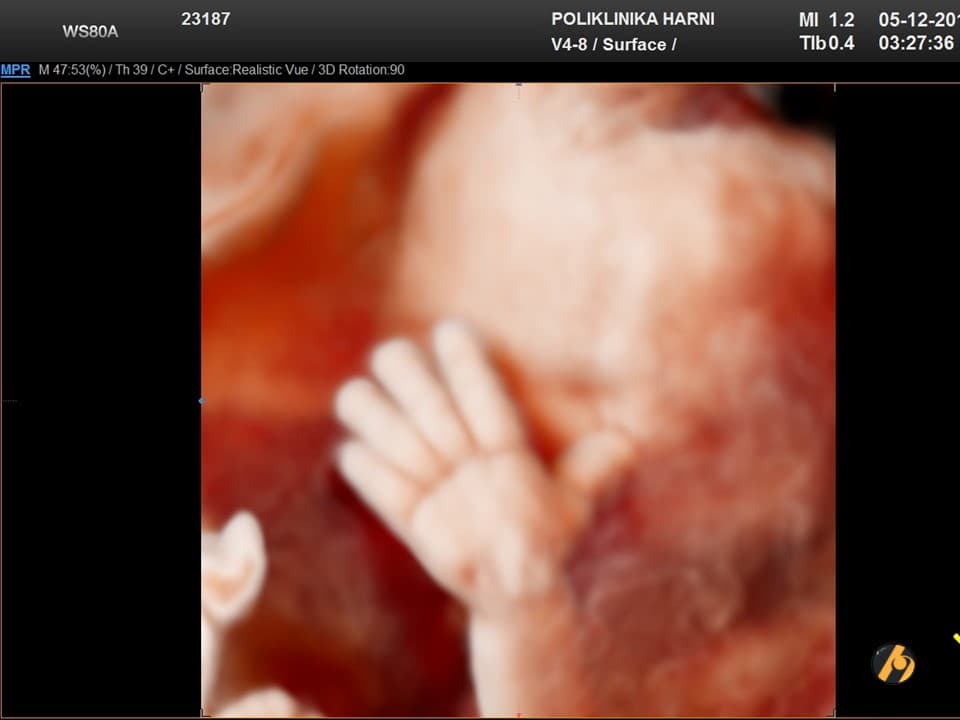

U 27. tjednu beba je duga oko 36 cm i teška približno 900–1000 g. Pluća još sazrijevaju, ali su šanse preživljavanja u slučaju prijevremenog poroda već visoke uz intenzivnu skrb.

U 27. tjednu beba je duga oko 36 cm, teška približno 900 do 1000 g i veličinom odgovara manjoj glavici repe. U sljedećim tjednima rast težine postat će sve brži, a beba će postupno dobivati zaobljeniji izgled.